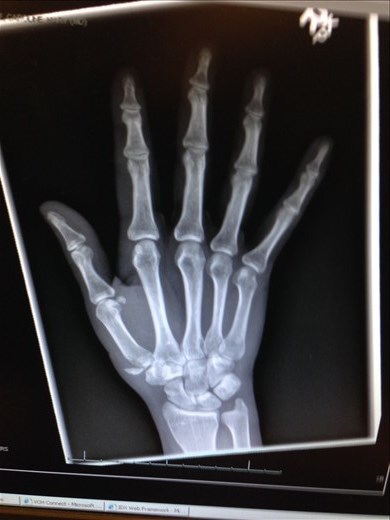

My hand

X-ray showing the fracture to the base of the thumb (chipped off piece of bone)